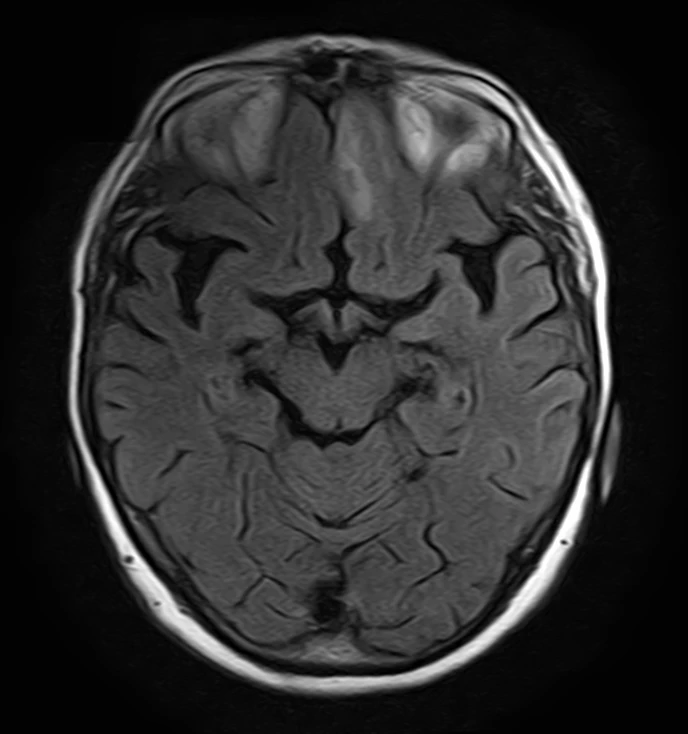

Менингиомы иногда не ходят одни. А по две, три и больше. Самая крупная слева в ЗЧЯ - хорошо видно место, из которого она растет: фокальные утолщения кости по краям и плоское основание опухоли (стрелки).